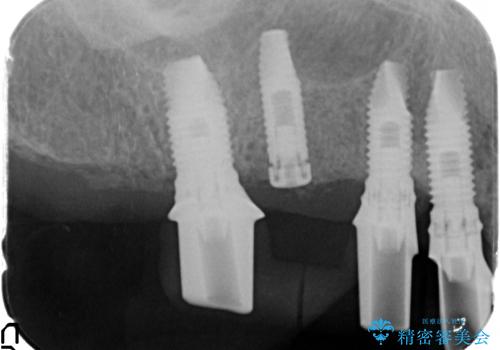

- 他院で1本インプラントを入れたまま治療に通うことができなくなり、途中からの治療を希望され来院されました。

既に埋入されているインプラントは位置が悪いのでそのまま骨内に留置することとし、新たに咬合機能を回復すべく3本のインプラントを埋入すると同時に吸収した骨幅を増やし、安定してインプラントで噛める環境整備を目指します。

- 120万円(インプラント×3 チタンカスタムアバットメント×3 メタルボンドクラウン×3 骨造成 歯肉移植)費用は治療当時の料金となります

インプラントが長持ちするために、インプラント周囲の十分な骨量・角化歯肉の存在・安定した咬合を一つづつ整備する治療を行いました。